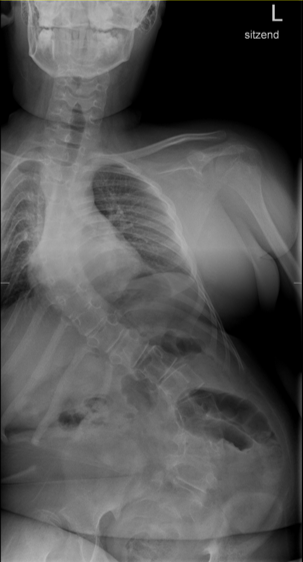

Überzähliger Halbwirbel bei einem 4 jährigem Jungen:

Mit Hilfe einer Wirbelsäulenganzaufnahme, einem Röntgenbild der kompletten Wirbelsäule, können der Krümmungswinkel sowie die Verdrehung der Wirbelkörper gemessen werden. Es sollte immer die gesamte Wirbelsäule auf einer Aufnahme abgebildet und nicht mehrere kleine Bilder angefertigt werden, da man die Krümmung sonst nicht exakt vermessen und die Statik beurteilen kann.

Für diese Wirbelsäulenganzaufnahmen braucht man spezielle, sehr teure Röntgenröhren, die natürlich nicht jeder Arzt hat. Deswegen kann es sein, dass du in ein spezialisiertes Wirbelsäulenzentrum überwiesen wirst. Die Winkel werden in „Gradzahlen nach Cobb“ angegeben, da Dr. Cobb diese Messmethode entwickelt hat. Vor einer Operation werden noch sogenannte Bending-Aufnahmen angefertigt. Du musst dich einmal so weit es geht nach links und dann nach rechts biegen. Danach kann man ausmessen, welche Krümmung schon steif (rigide) ist und welche noch so flexibel ist, dass sie sich noch selbständig ausgleichen kann. Das ist vor allem für die OP-Planung wichtig.